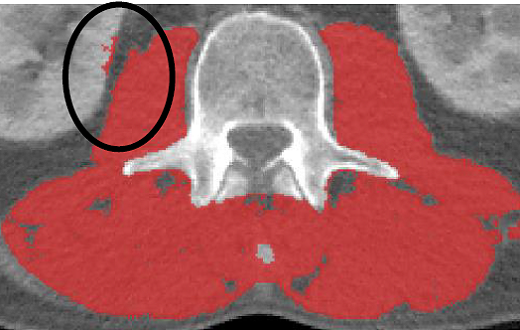

·For skeletal muscle analysis, all muscles at the L3 region will be analyzed (TAG 1- Red, HU Range: -29 to +150)

·Fascia bundles that connect to muscle should not be analyzed as muscle

·Be careful not to include non muscle structures touching the psoas or other muscles